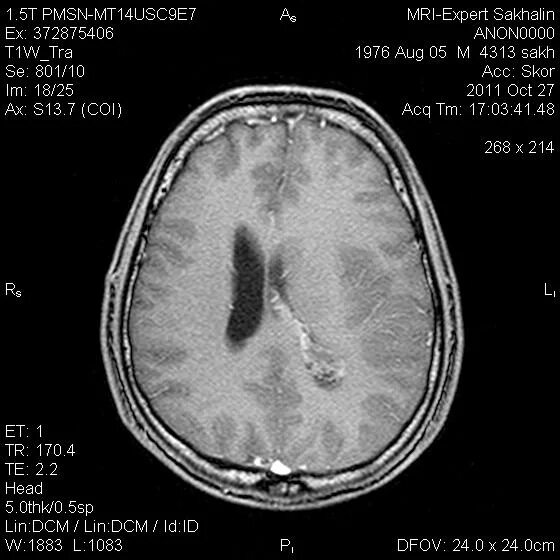

Глиоз прогнозы